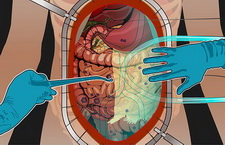

萬芳醫院從2000年開始嘗試第一例的腫瘤減量手術合併腹腔熱化療,治療胃癌合併有腹腔轉移的病例,並於2002年開始常規的施行此項治療, 隨後並擴展到其他各式各樣的癌症。

隨著經驗的累積,併發症及手術死亡的比例逐年下降,目前已超越許多其他國家的醫院。並不是每一位病患都適合接受此項治療,如您有治療上的需求,歡迎預約前來諮詢。

謝茂志 醫師 提供

Wan-Fang Hospital started to perform CRS (cytoreduction surgery) plus HIPEC (hyperthermic intraperitoneal chemotherapy) at 2000, to treat the first case of gastric cancer with peritoneal metastasis. Since 2002, it became a regular procedure and treat many kinds of cancers at the present.

Till now, we are experienced with this procedure. The complication and death rates declined and even better than many other hospitals in the world. It is not suitable for every patient. We welcome you to make an appointment for further consultations.